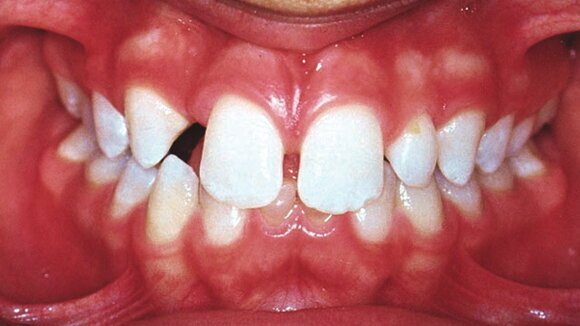

Extra-oral examination revealed a well-balanced face with normal facial profile and normal skeletal dental base relationships. Intra-oral examination revealed a Class I malocclusion in the late mixed dentition (Figs. 1a–c).

A 2 mm maxillary median diastema was present and the maxillary left lateral incisor, 22, was microdontic. Oral hygiene and gingival status were good and no caries was found.

Radiographic examination confirmed that twelve teeth were developmentally missing: 18, 17, 12, 25, 27, 28, 31, 35, 38, 41, 45 and 48. Significant external root resorption was found in the retained primary teeth, 75 and 85 (Fig. 1b).